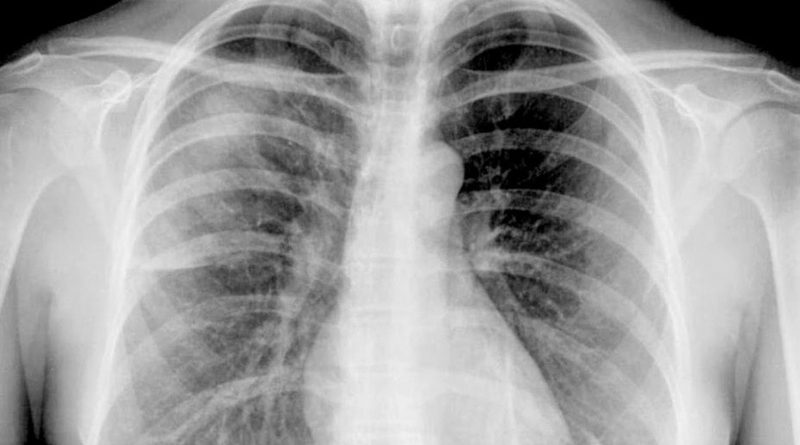

PREOCUPACIÓN MUNDIAL: AUMENTARÁN LOS CASOS DE CÁNCER DE PULMÓN EN MUJERES CASI UN 45%

La tasa mundial de mortalidad por cáncer de pulmón en mujeres aumentará en un 43 % entre 2015 y 2030, mientras que en cáncer de mama disminuirá un 9 %, según un estudio realizado en 52 países por un equipo internacional de cientificos